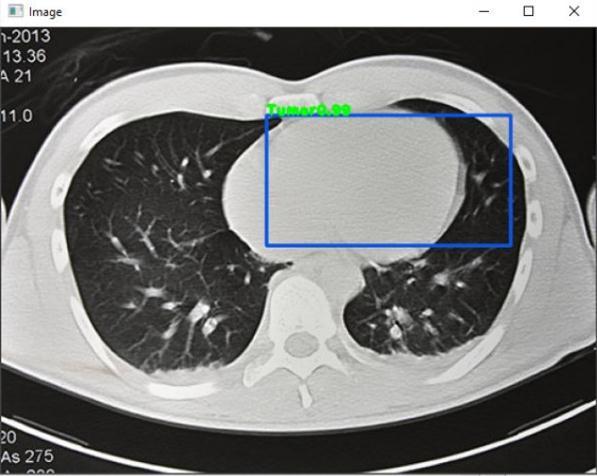

Fig 3 :TomorDetectedinLungs Fig 4 :ClotDetectioninLung Fig 4 :Clot&TumorDetectioninLung Fig – 5 :TumorDetectioninLung

finaloutcome.